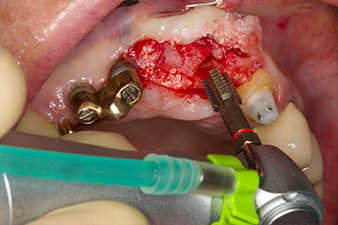

initial radiological findings

Fig. 1: The initial radiological findings revealed a splinted crown restoration requiring replacement. When the restoration was removed, teeth 21 and 22 were unintentionally extracted along with it.

The x-ray revealed horizontal bone loss around teeth 21 and 22 (Fig. 1). When the crown block was removed, these teeth were unintentionally extracted with it.